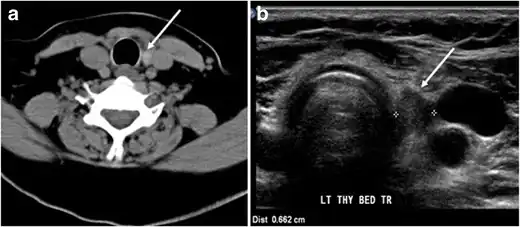

Fig. 8. A 48-year-old male patient post total thyroidectomy with PTC recurrence. a Transverse greyscale ultrasound of the neck demonstrates a left thyroid bed heterogeneous, predominantly hypoechoic irregular lesion with calcifications (white arrow). b A spot image of iodine 123 total body scan of the neck demonstrate a focus of abnormal radiotracer uptake at the left thyroid bed (Black arrows) between the annotated markers. c Enhanced axial CT scan of the neck demonstrates an enhancing large left thyroid bed mass (white arrow) with no calcifications. The lesion exerts a mass effect on the oesophagus (black arrow) and is inseparable from the trachea.[1] -